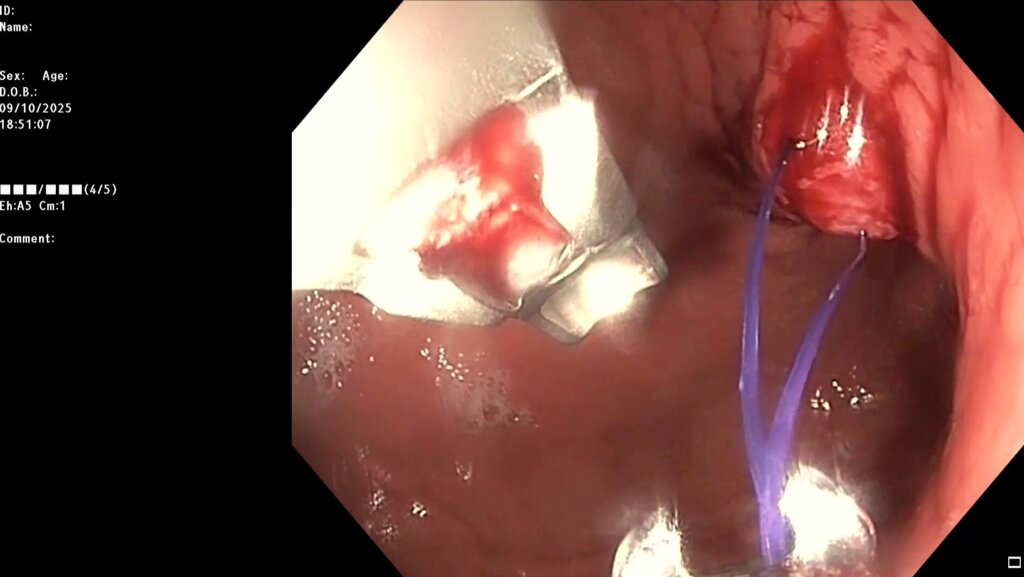

После предварительного обследования произведена операция: ESG + АПК (APC) свода; всего использовано 6 швов, время процедуры ≈ 120 минут.

Под видеоконтролем выполнена эндоскопическая рукавная гастропластика: сшивание стенок желудка при помощи аппарата Overstitch Boston Scientific по длине тела с целью уменьшения объёмов съедаемой пищи.